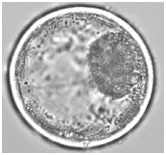

White light image (left), fluorescence FCI image (center) and hyperspectral fluorescence image (right) images of a bovine embryo after staining with Nile Red, acquired on the XploRA INV. The hyperspectral image illustrates the stain in different polarity states. Data courtesy of Prof. Igor Chourpa, Université de Tours, France.